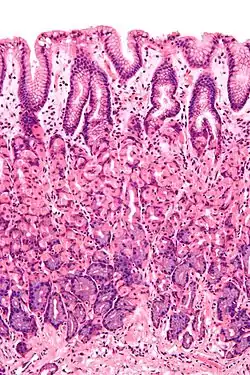

The epithelium, the most exposed part of the mucosa, is a glandular epithelium with many goblet cells. Goblet cells secrete mucus, which lubricates the passage of food along and protects the intestinal wall from digestive enzymes. In the small intestine, villi are folds of the mucosa that increase the surface area of the intestine. The villi contain a lacteal, a vessel connected to the lymph system that aids in the removal of lipids and tissue fluids. Microvilli are present on the epithelium of a villus and further increase the surface area over which absorption can take place. Numerous intestinal glands as pocket-like invaginations are present in the underlying tissue. In the large intestines, villi are absent and a flat surface with thousands of glands is observed. Underlying the epithelium is the lamina propria, which contains myofibroblasts, blood vessels, nerves, and several different immune cells, and the muscularis mucosa which is a layer of smooth muscle that aids in the action of continued peristalsis and catastalsis along the gut.

- In the small intestine, epithelium is simple columnar and specialised for absorption. It is organised into plicae circulares and villi, and the enterocytes have microvilli. The microvilli create a brush border that increases the area for absorption. In the ileum there are occasionally Peyer's patches in the lamina propria. Brunner's glands are found in the duodenum but not in other parts of the small intestine.[1]

Cross-section histology of intestinal villi of the human terminal ileum.